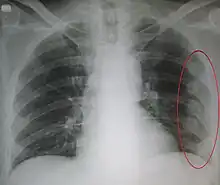

| An X ray showing multiple old fractured ribs of the person's left side as marked by the oval | |

Plain X-rays often pick up displaced fractures but often miss undisplaced fractures.[13] CT scanning is generally able to pick up both types of fractures.[13]

Right sided pneumothorax and rib fractures